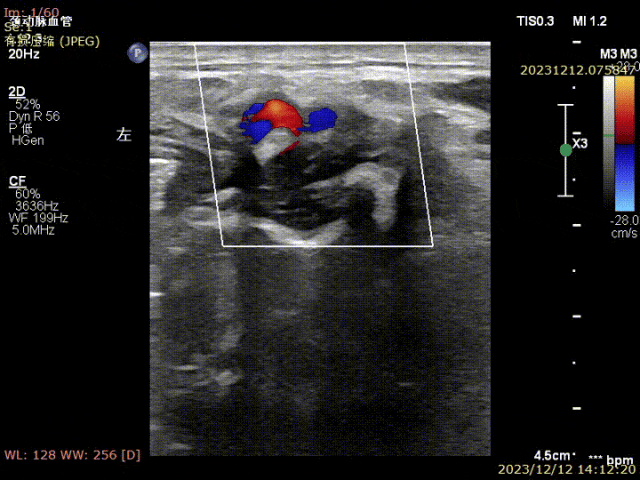

姜坤主任接诊后做彩超发现患者左侧颈总动脉分叉处硬化斑块钙化严重,颈内动脉起始部重度狭窄(狭窄程度>90%),且斑块为易损斑块。

▲患者术前颈部血管超声可见颈动脉斑块,狭窄局部血流速度明显减慢